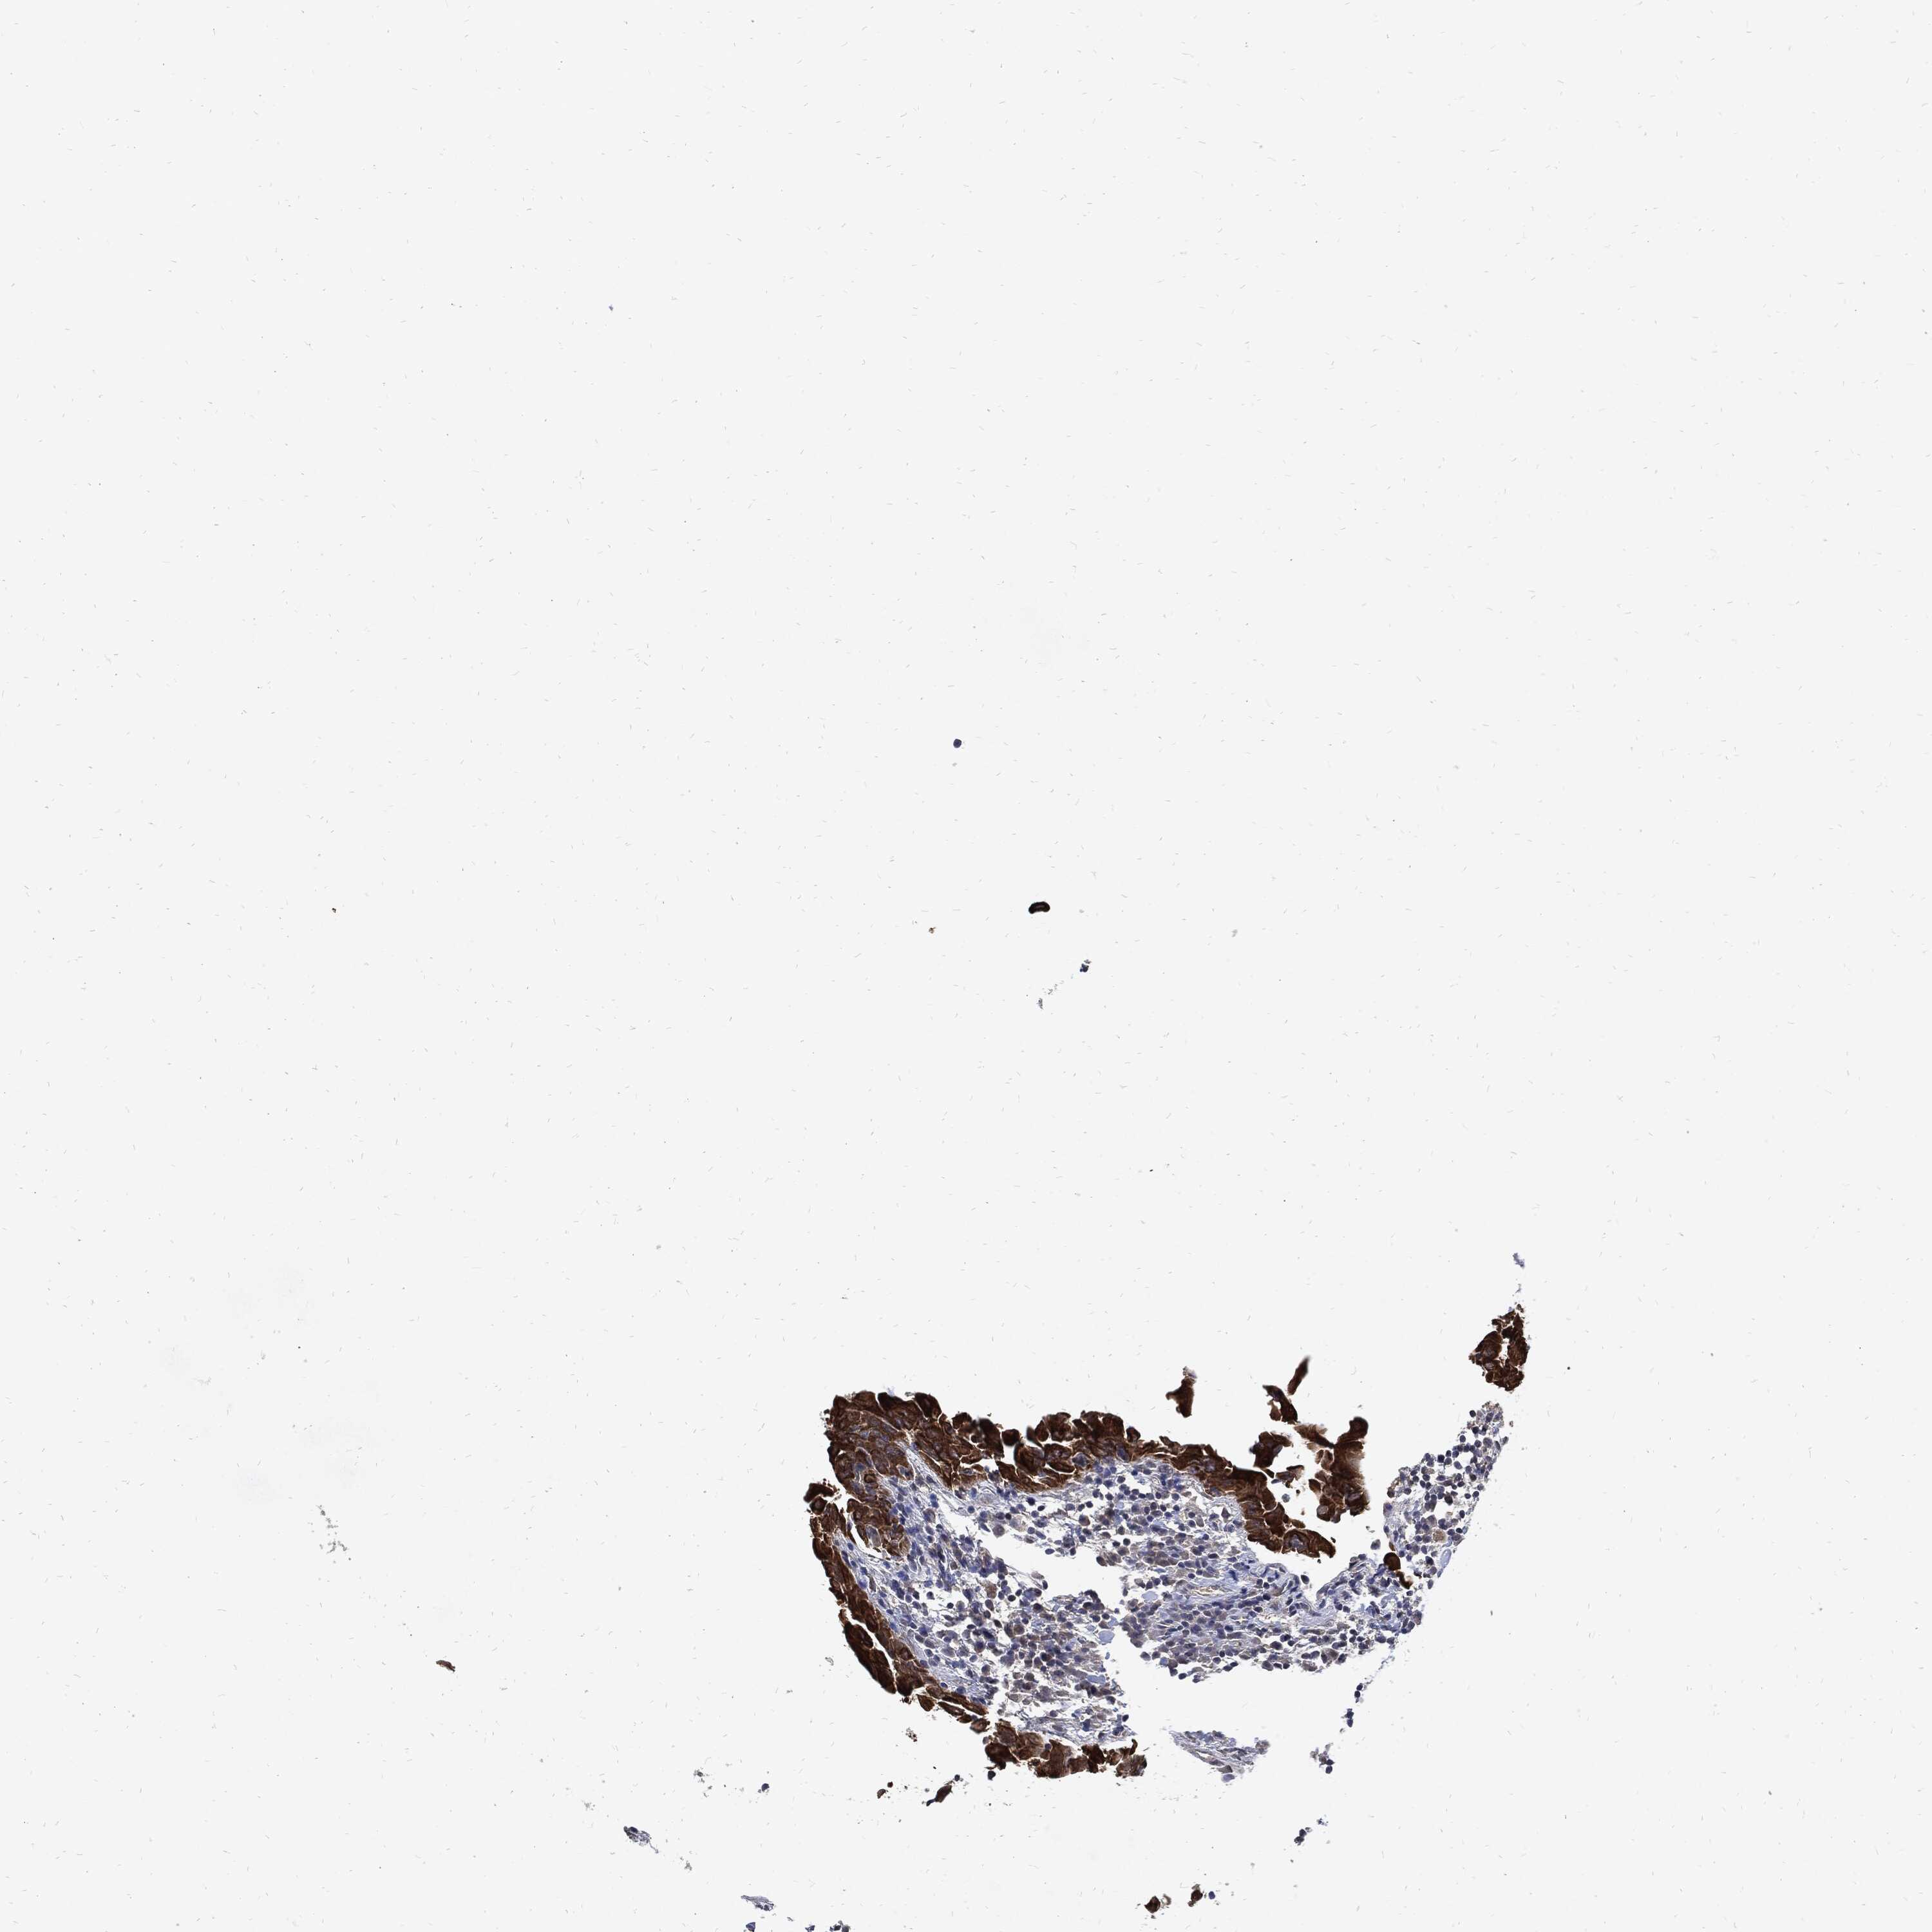

THYROID CANCER - Protein expressioni

A mouse-over function shows sample information and annotation data. Click on an image to view it in a full screen mode. Samples can be filtered based on level of antibody staining by selecting one or several of the following categories: high, medium, low and not detected. The assay and annotation is described here.

Note that samples used for immunohistochemistry by the Human Protein Atlas do not correspond to samples in the TCGA dataset.

Antibody stainingi

Antibody staining in the annotated cell types in the current human tissue is reported as not detected, low, medium, or high, based on conventional immunohistochemistry profiling in selected tissues. This score is based on the combination of the staining intensity and fraction of stained cells.

Each image is clickable and will lead to virtual microscopy that enables deeper exploration of all samples and also displays staining intensity scores, fraction scores and subcellular localization as well as patient and tissue information for each sample.

Antibody HPA034635

Antibody HPA069977

Antibody HPA071875

Antibody CAB009108

Staining

High

Medium

Low

Not detected

Intensity

Strong

Moderate

Weak

Negative

Quantity

>75%

75%-25%

<25%

None

Location

Nuclear

Cytoplasmic/membranous

Cytoplasmic/membranous,nuclear

Papillary adenocarcinoma, NOS

Follicular adenoma carcinoma, NOS